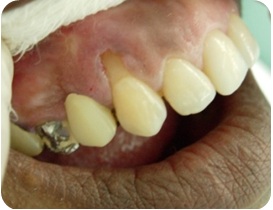

- Figura 1A (Português (Brasil))

- Figura 1B (Português (Brasil))